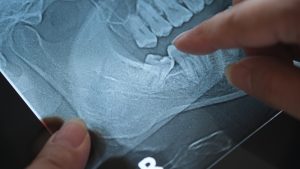

If X-rays show wisdom teeth may cause or are causing issues, removal may be recommended to protect the rest of your smile.

We use detailed imaging to understand the position of your wisdom teeth and determine whether treatment is needed.